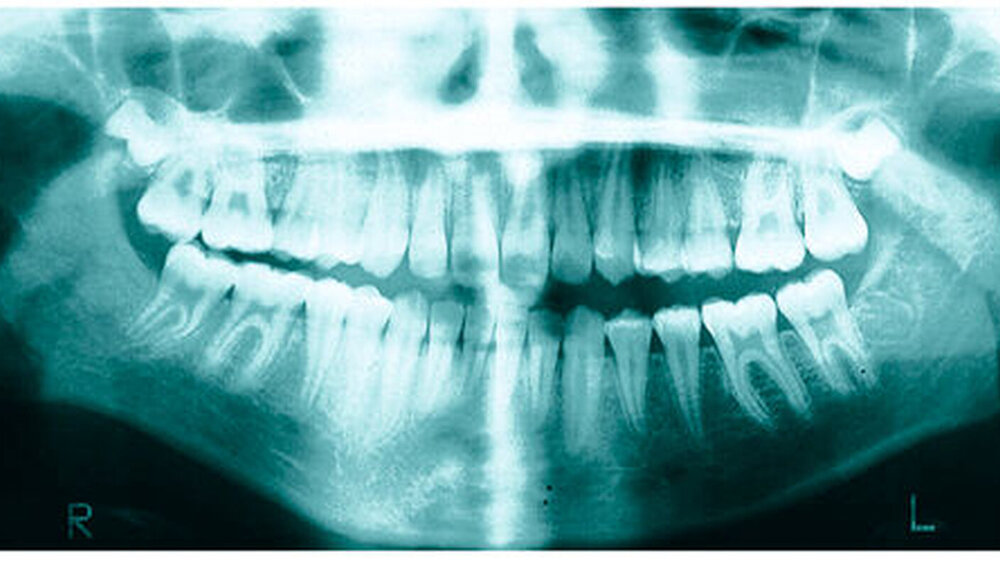

Bereits 2004 wies Carla Evans [Evans, 2005] auf das Risikomanagement bei Allgemeinerkrankungen hin und stellte am Beispiel der JIA dar, dass Unterkieferrücklagen und frontal offene Bisse aus der Kiefergelenkzerstörung entstehen können. Die Röntgenaufnahmen einer JIA-Patientin mit oligoartikulärer Form und Beteiligung des rechten Kiefergelenkes zeigen den typischen Verlauf sehr gut. Bei ursprünglich sehr dezenten Befunden, wie einer s-förmigen Mundöffnung von 44 mm, einer geringen Mittenabweichung um 2 mm nach rechts und einem frontal offenem Biss klagte sie über Schmerzen beim Essen, was den Anlass zur weiteren Diagnostik bot. Die erste Panoramaröntgenschichtaufnahme (Abbildung 1a-c) zeigt auf der rechten Seite einen abgeflachten Kondylus und eine bereits verstrichene Fossa condylaris. Ein Jahr später vermittelt das Fernröntgenseitenbild (Abbildung 1d) trotz fortschreitender kondylärer Resorption ein harmonisches Bild, während nach drei Jahren bei voranschreitendem Abbau des rechten Kondylus (Abbildung 1e) eine Rücklage der Mandibula und eine Bissöffnung manifest sind (Abbildung 1f).

Mithilfe der Panoramaröntgenschichtaufnahme lässt sich in bis zu 67 Prozent der Fälle bereits eine Kiefergelenkdestruktion bei Kindern mit JIA feststellen [Küseler et al., 1998; Twilt et al., 2004; Abramowicz et al., 2014]. Eigene Untersuchungen bestätigten die Eignung als Screening-Verfahren [Mäckelmann, 2008].

Bei 152 durchschnittlich 12-jährigen Rheumapatienten wurden die kondyläre Morphologie und Symmetrie beziehungsweise Asymmetrie im Vergleich zu einer Kontrollgruppe anhand der OPG analysiert. Zur Analyse erfolgte die Zuordnung zu vier morphologischen Graden je Kondylus (Abbildung 3a-d). Bei 45 Prozent der Rheumapatienten waren morphologische Veränderungen im Rahmen kondylärer Resorption unterschiedlicher Ausprägung zu finden. Die „Kontrollpatienten“ ohne JIA zeigten nur zu 14 Prozent formatypische Kondylen. Der Unterschied zwischen den beiden Gruppen war signifikant. Daher sollte bei der Routineauswertung von Panoramaröntgenschichtaufnahmen auf diese Anzeichen geachtet werden, insbesondere auch unter dem Aspekt, dass laut Assaf [2011] durchschnittlich 4,3 Jahre zwischen Erstmanifestation der JIA und Erstvorstellung in der Rheumasprechstunde des UKE liegen.